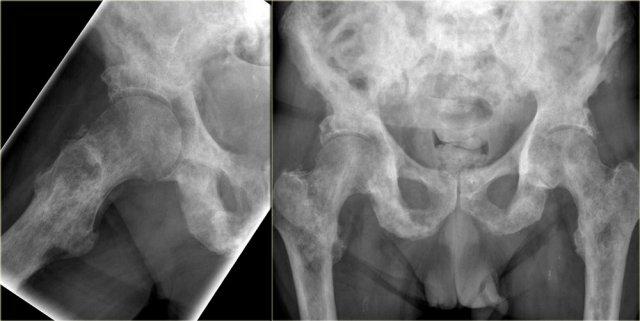

Trong trường hợp này, chúng ta thấy bộ ba triệu chứng đặc trưng bệnh lý gồm giãn nở xương, dày vỏ xương và dày bè xương trong giai đoạn hỗn hợp tiêu xương và xơ cứng xương của bệnh Paget nửa xương chậu phải.